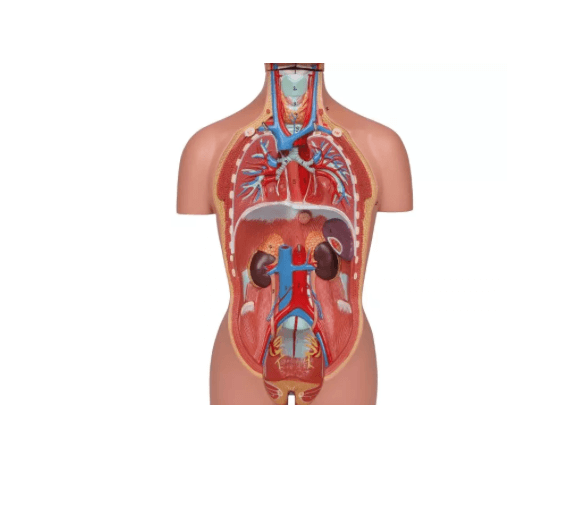

Dieses Torso-Modell in ca. ½ Lebensgröße bietet eine kompakte und dennoch äußerst detailreiche Darstellung der menschlichen Anatomie. Ideal geeignet als Schreibtischmodell, für den Anatomieunterricht oder zur Patientenaufklärung, vermittelt es anschaulich die Lage und den Aufbau innerer Organe – inklusive männlicher und weiblicher Geschlechtsorgane. Die verschiedenen Komponenten lassen sich entnehmen und untersuchen, was das Modell besonders nützlich für den Einstieg in die menschliche Anatomie macht. Lieferung erfolgt auf stabiler Grundplatte inklusive beschrifteter Anleitung.

Modellteile im Überblick:

Grundkörper mit zwei Kopfhälften

Eine Kopfhälfte mit herausnehmbarem Gehirn

Zwei Lungenhälften

Herz (zweiteilig zerlegbar)

Magen

Leber

Darmpaket mit abnehmbarem Blinddarmdeckel

Weibliche Geschlechtsorgane (zweiteilig)

Männliche Geschlechtsorgane (zweiteilig)